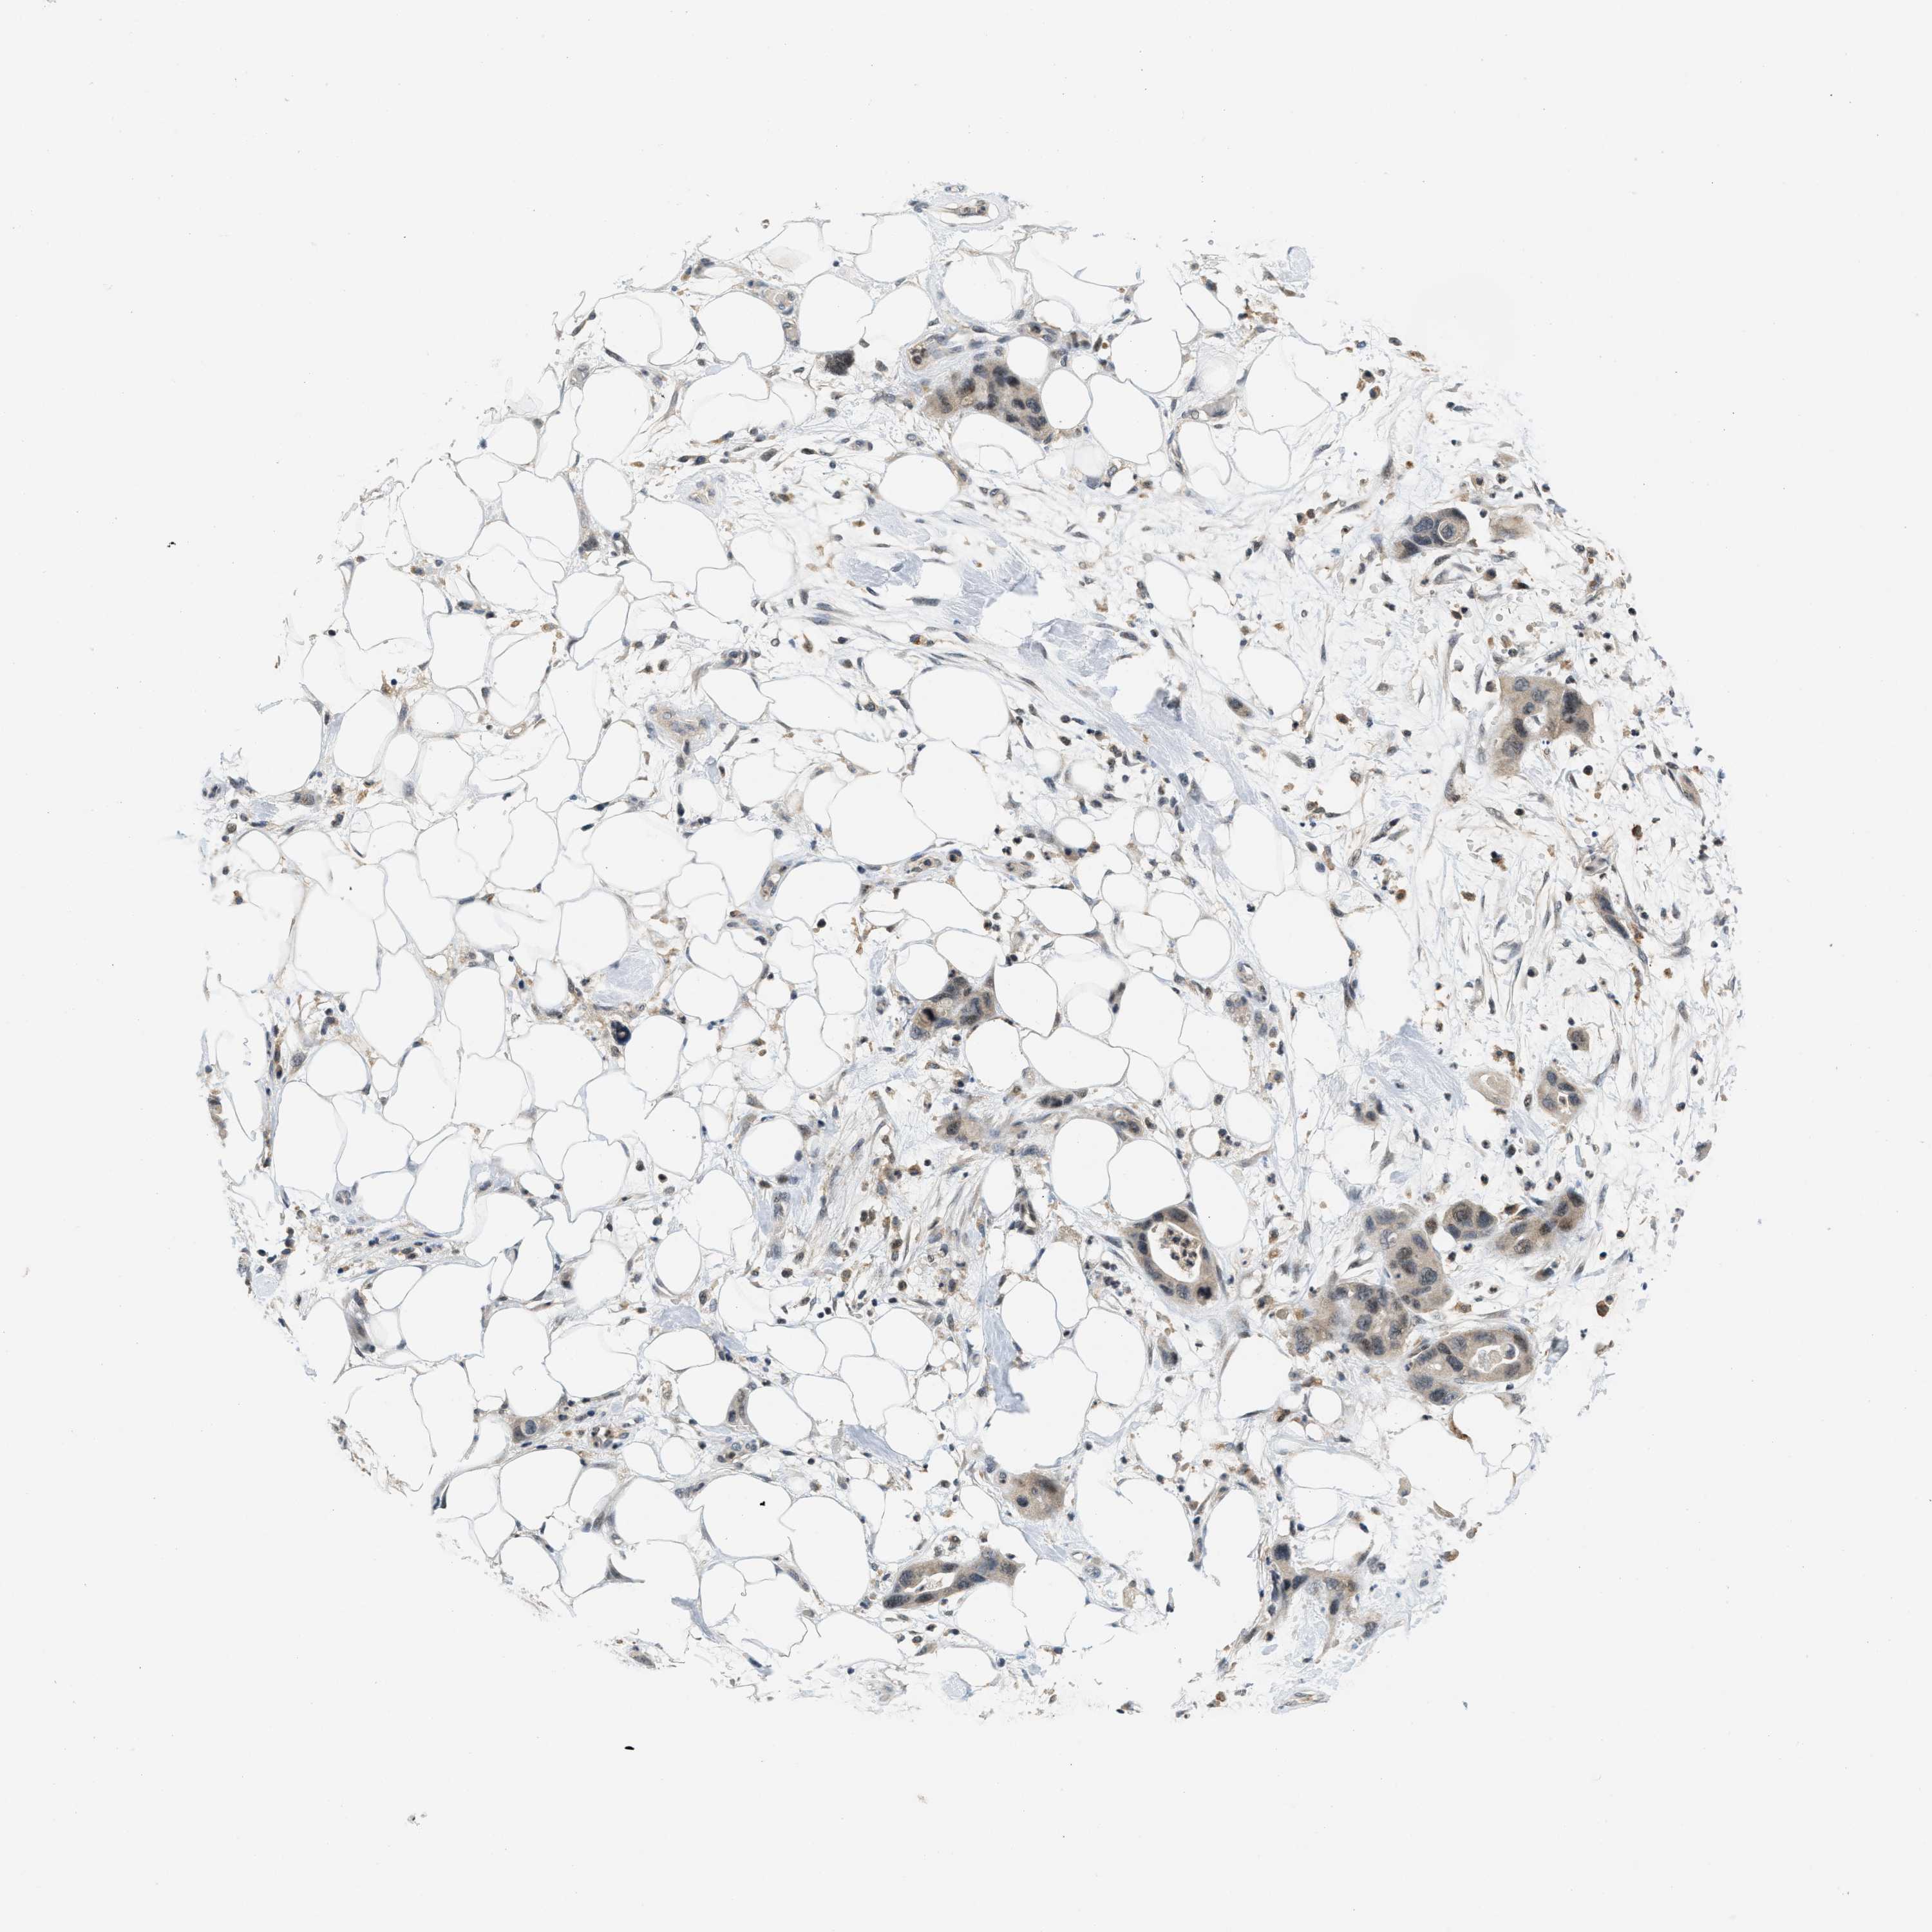

PANCREATIC CANCER - Protein expressioni

A mouse-over function shows sample information and annotation data. Click on an image to view it in a full screen mode. Samples can be filtered based on level of antibody staining by selecting one or several of the following categories: high, medium, low and not detected. The assay and annotation is described here.

Note that samples used for immunohistochemistry by the Human Protein Atlas do not correspond to samples in the TCGA dataset.

Antibody stainingi

Antibody staining in the annotated cell types in the current human tissue is reported as not detected, low, medium, or high, based on conventional immunohistochemistry profiling in selected tissues. This score is based on the combination of the staining intensity and fraction of stained cells.

Each image is clickable and will lead to virtual microscopy that enables deeper exploration of all samples and also displays staining intensity scores, fraction scores and subcellular localization as well as patient and tissue information for each sample.

Antibody CAB016136

Antibody CAB017773

Staining

High

Medium

Low

Not detected

Intensity

Strong

Moderate

Weak

Negative

Quantity

>75%

75%-25%

<25%

None

Location

Nuclear

Cytoplasmic/membranous

Cytoplasmic/membranous,nuclear

Adenocarcinoma, NOS

Adenocarcinoma, metastatic, NOS